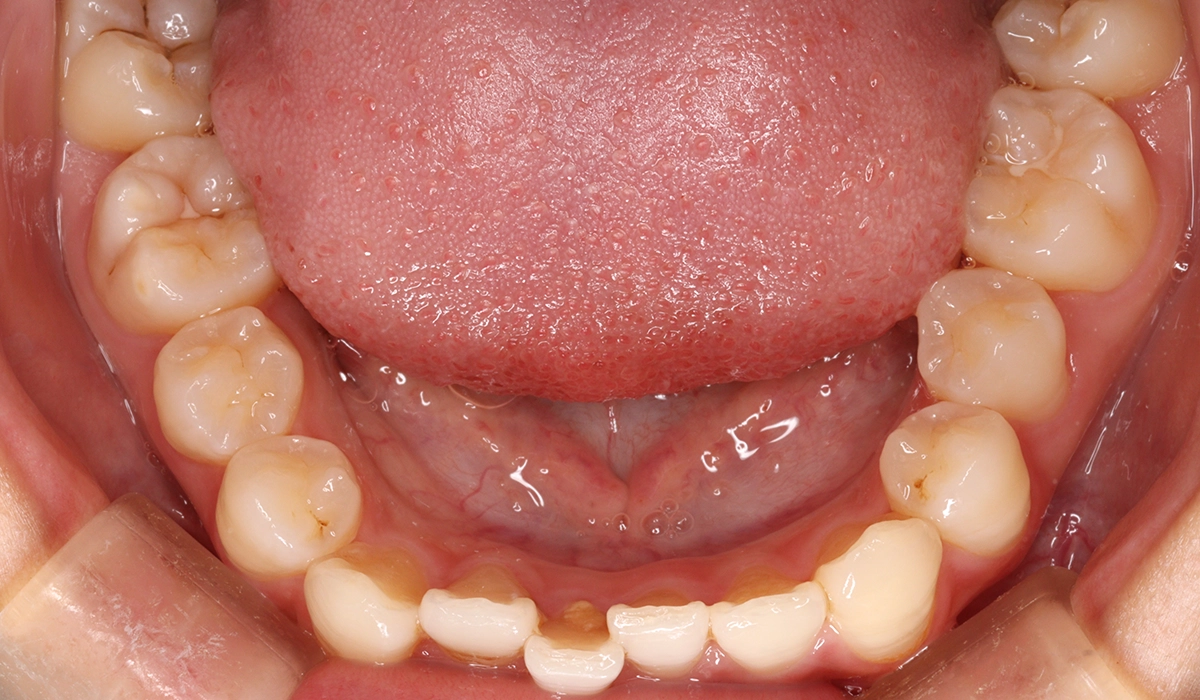

術前:下顎前歯部寄り

術後:オーバージェット